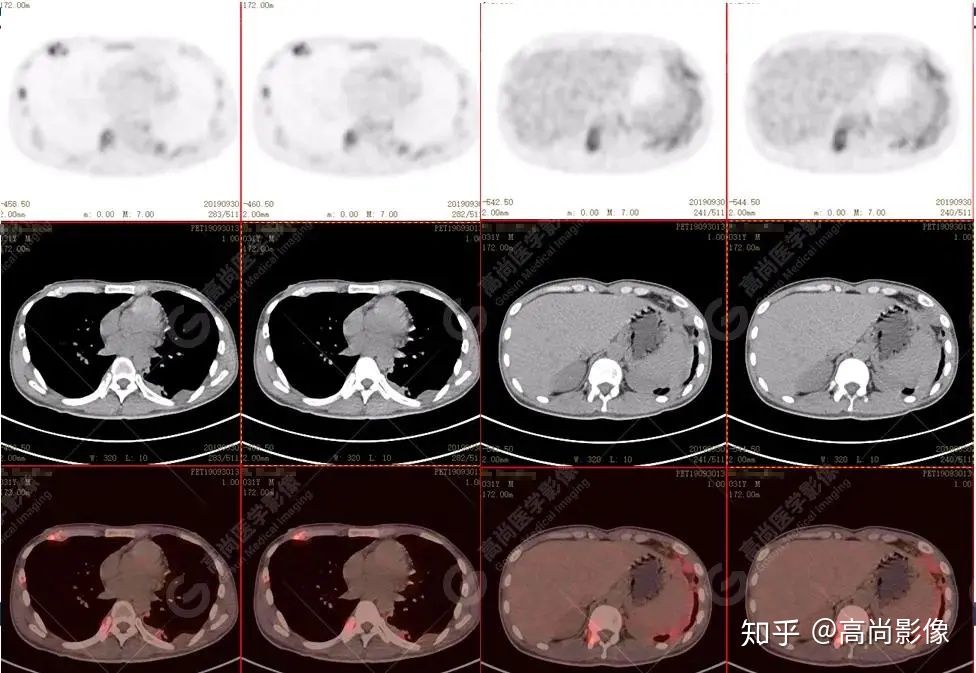

脊柱多發(fā)椎體及附件骨質(zhì)破壞,代謝不均性增高

全身多處骨質(zhì)破壞,代謝不均性增高

【PET/CT提示】雙肺、左側(cè)胸膜多發(fā)結(jié)節(jié)影,全身多處骨質(zhì)破壞,全身多發(fā)淋巴結(jié)腫大,代謝攝取不均勻性增高。

骨結(jié)核:好發(fā)青少年,好發(fā)部位為脊柱,又稱Pott病,表現(xiàn)為椎體松質(zhì)骨破壞,骨皮質(zhì)失去完整性,可見死骨和輕微骨增生和塌陷,早期椎間盤無破壞,后期發(fā)生破壞,椎間隙變窄,可伴椎旁冷膿腫,其次是膝、髖、肘關(guān)節(jié)。